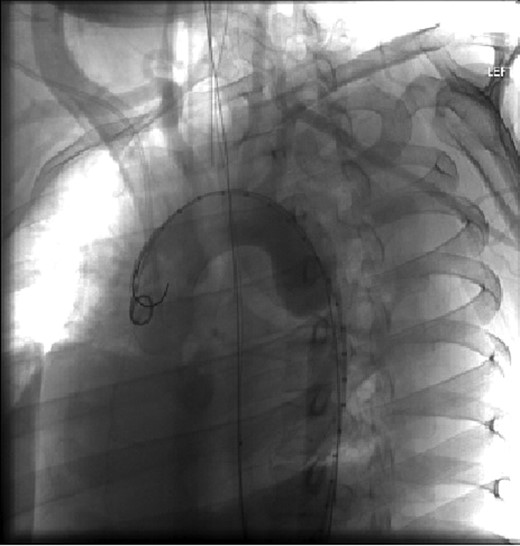

The patient was taken emergently to the vascular hybrid room where the left common femoral was accessed percutaneously. A 26–21 mm diameter tapered Gore Tag® endograft was positioned at the left subclavian artery and deployed. The pseudoaneurysm was sealed and the transection resolved (Figs 2 and 3).

Visualization of the aortic arch and thoracic aorta after stent placement.